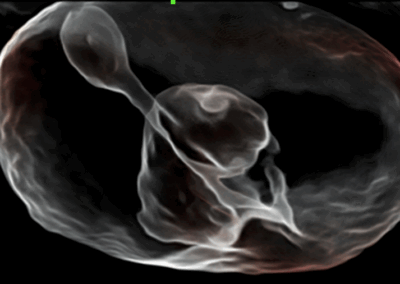

Nuewa i8

El Nuewa I8, ofrece una claridad de imagen inigualable, elevando tu confianza y eficiencia a nuevas alturas. Diseñado con el máximo cuidado, minimiza la fatiga y maximiza la conveniencia a lo largo del proceso de operación.

Impulsado por la innovadora plataforma ZST + y un conjunto completo de soluciones inteligentes, el Nuewa I8 ofrece una claridad de imagen inigualable, impulsando tu confianza y eficiencia a nuevas cotas. Diseñado con la máxima atención al detalle, minimiza la fatiga y maximiza la comodidad durante todo el proceso quirúrgico.